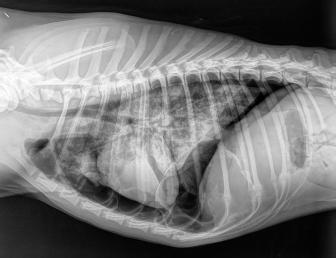

No complication due to ABP was observed. Control thoracic X-rays were obtained 24 hours and 1 week after the procedures, which did not show any signs of relapse in dogs 1 through to 4 (Fig. 4).

Fig. 4. Right-lateral thoracic radiographic of the same dog in Figure 3, 24 hours after autologous blood patch pleurodesis.